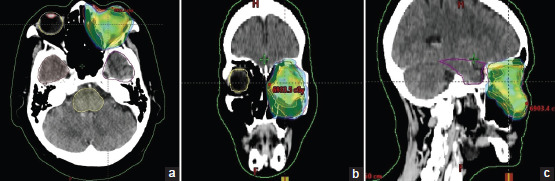

眼眶鳞状细胞癌(SCC)非常罕见。文献中仅报道了十几例此类病例。由于其罕见性,标准治疗方法尚未确定,但大多数都采用手术治疗。在此,我们报告了一例原发性眼眶 SCC 病例,患者是一名 56 岁的女性,仅接受了放射治疗(RT)。临床和影像学检查均未发现身体其他部位可能存在原发性恶性肿瘤,最终诊断为局部晚期原发性眼眶 SCC。患者接受了强度调节 RT 治疗,总剂量为 66Gy,分 33 次进行,治疗结束后疼痛得到了很好的缓解。反应评估成像显示治疗完全反应。随访 2 年,患者仍健在,无疾病,未受影响的眼睛视力正常。总之,原发性眼眶 SCC 非常罕见,可以通过 RT 成功治疗。

Squamous cell carcinoma (SCC) arising from the orbit is a rare entity. Only a dozen of such cases are reported in the literature. Owing to its rarity, standard treatment is not defined, but most are treated with surgery. Herewith, we report the case of primary orbital SCC, in a 56-year-old female treated with radiotherapy (RT) alone, who presented with features of left-sided painful blind eye of 4 months' duration. Clinical and imaging studies pointed to no other possible primary malignancy elsewhere in the body, and a final diagnosis of locally advanced primary orbital SCC was made. The patient was treated with intensity-modulated RT, to a total dose of 66Gy in 33 fractions and completed the treatment with good pain relief. Response assessment imaging showed a complete response to treatment. At 2-year follow-up, the patient is alive, without disease and with normal vision in the unaffected eye. To conclude, primary orbital SCC is rare and can be treated successfully with RT.